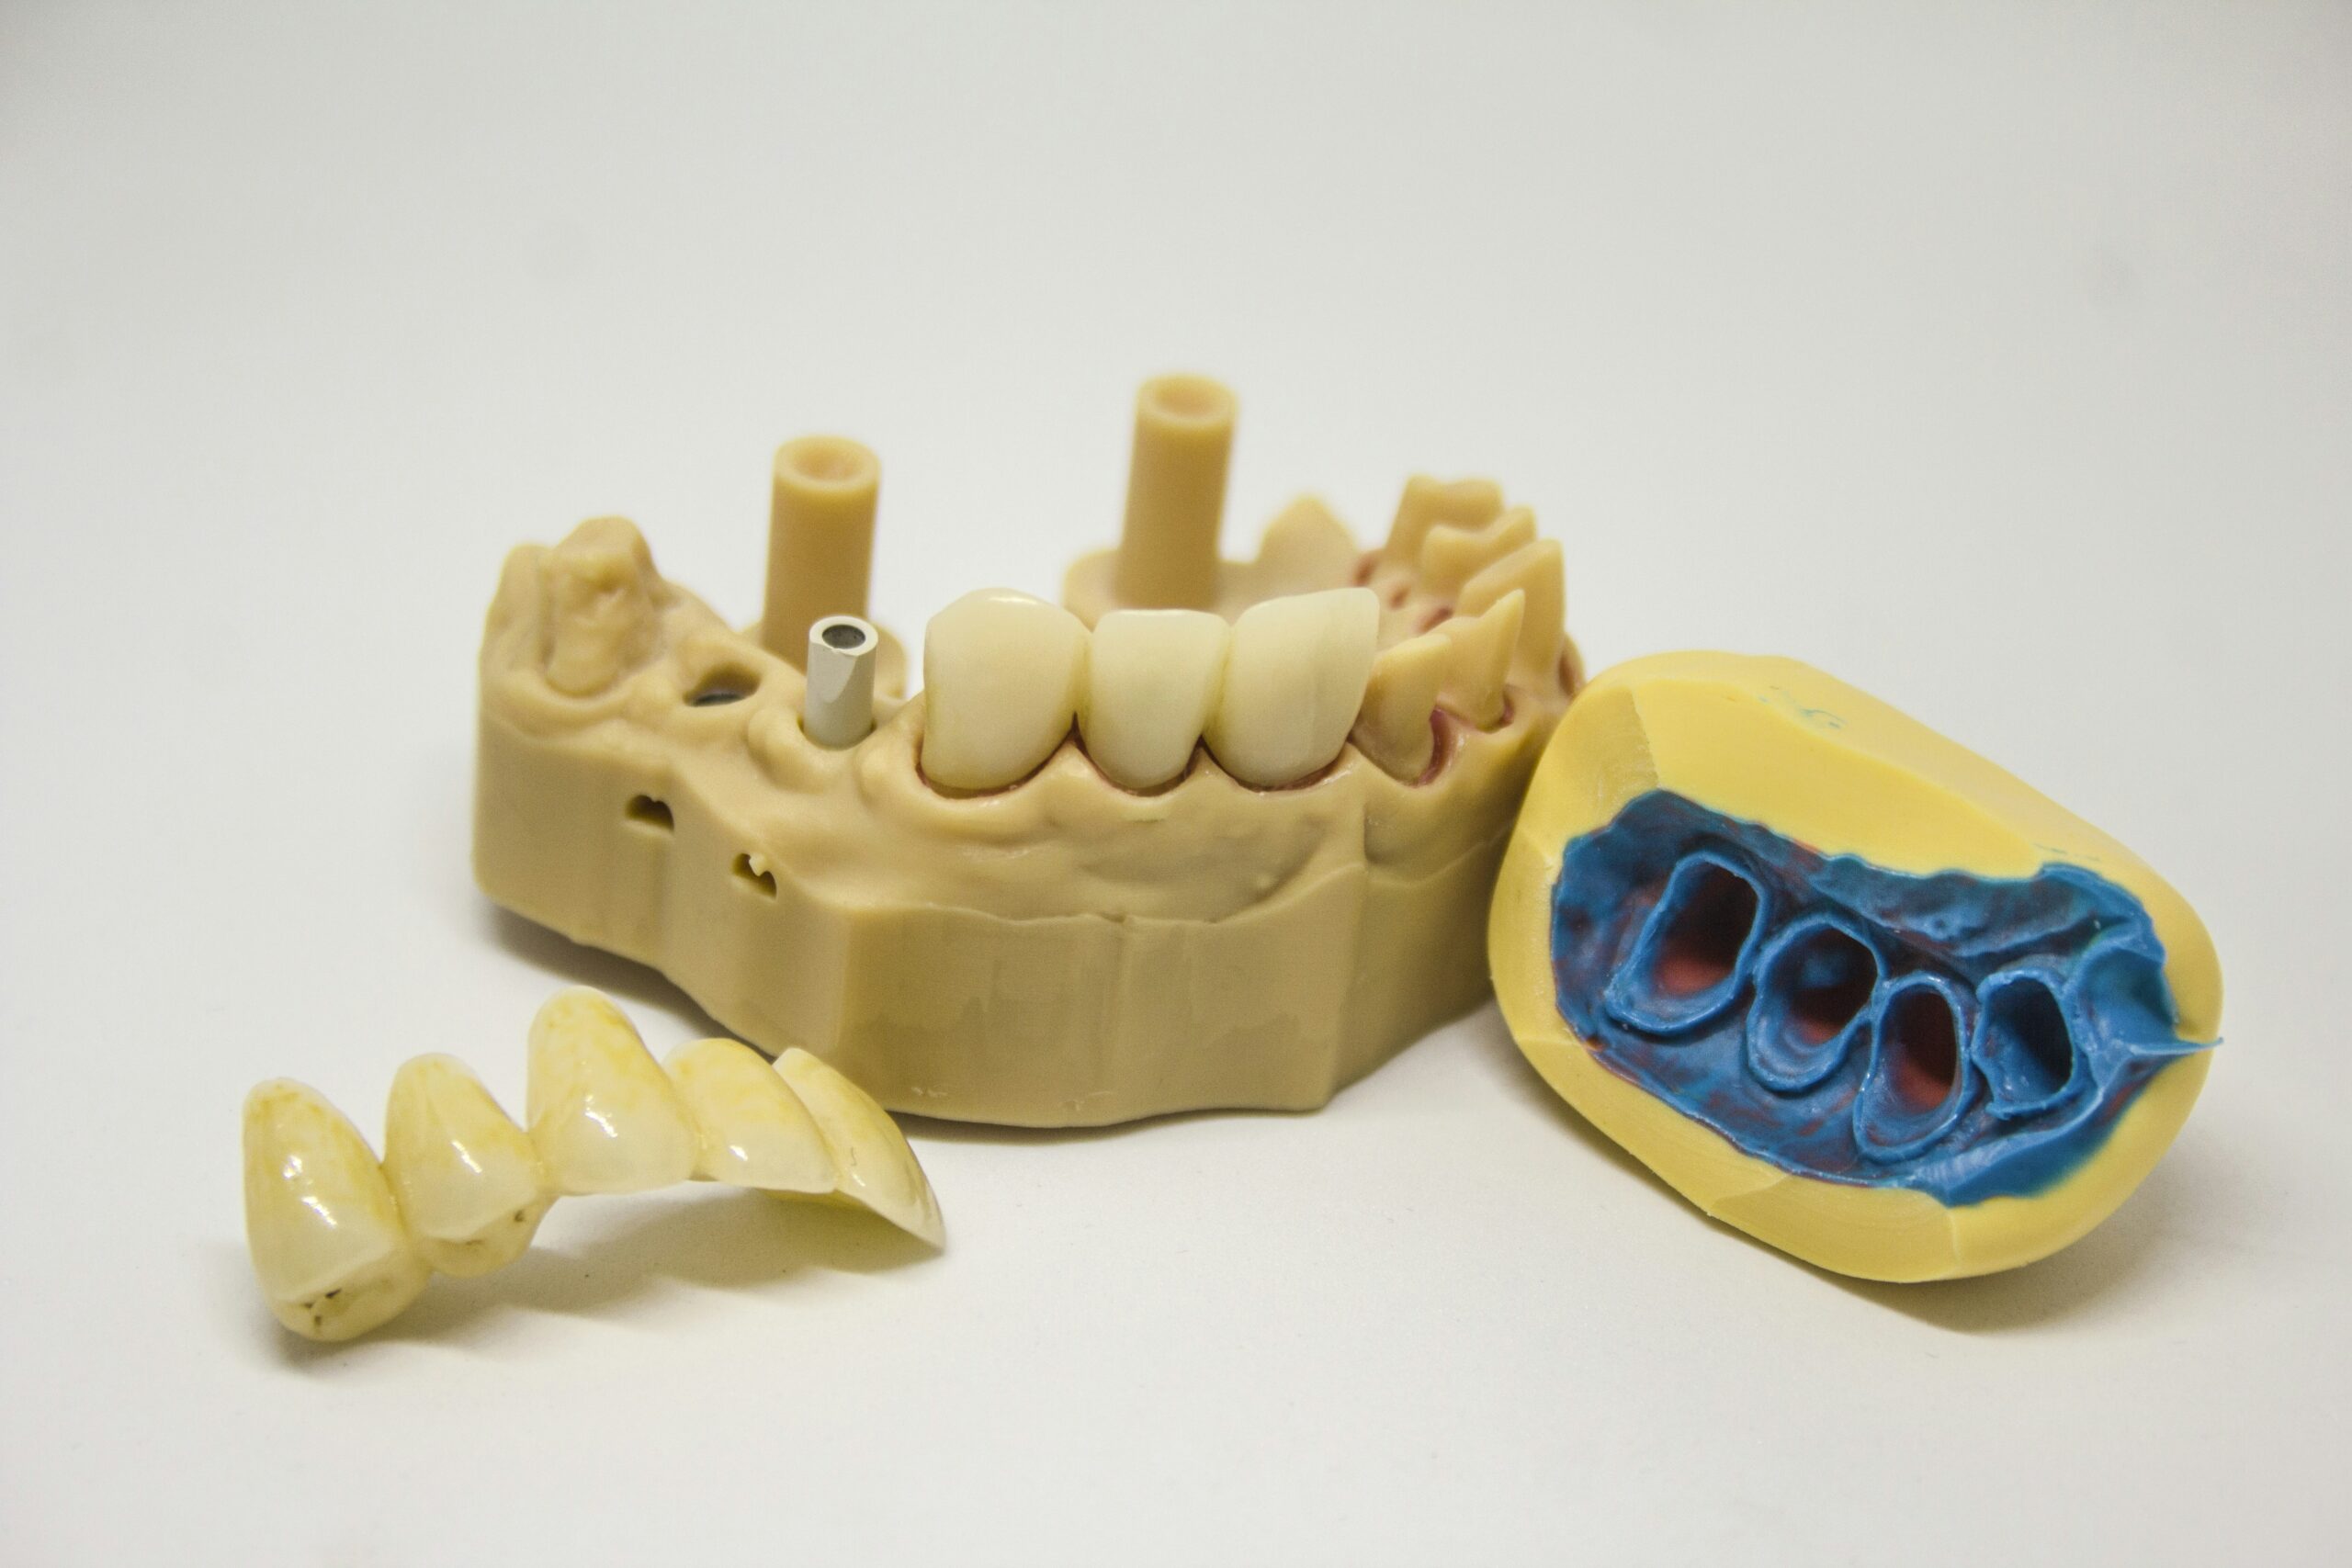

Dental implants

Dental implants are a permanent solution for missing teeth. They consist of artificial tooth roots that are surgically placed into the jawbone, providing a strong foundation for replacement teeth. Dental implants not only restore the appearance of a full smile but also improve chewing and speaking abilities.

Dental implants

Dental implants are a permanent solution for replacing missing teeth. They consist of titanium posts that are surgically placed into the jawbone, acting as artificial tooth roots. A crown, bridge, or denture is then attached to the implants, resulting in a natural-looking and functional tooth replacement.

3D imaging and scanning

3D imaging and scanning technology have revolutionized the field of cosmetic dentistry. Dentists can use cone beam computed tomography (CBCT) scans to create highly detailed 3D images of a patient’s teeth, gums, and jaw structures. This allows for precise treatment planning and ensures accurate placement of dental implants, as well as other advanced cosmetic dental procedures.